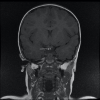

Figure 3. Coronal T1-weighted MRI section showing an ectopic posterior pituitary gland appearing in hypersignal T1 (thin white arrow)

Figure 4

Figure 4. Axial T1-weighted MRI section showing an ectopic posterior pituitary gland found under the floor of the third ventricle, behind the optic chiasma